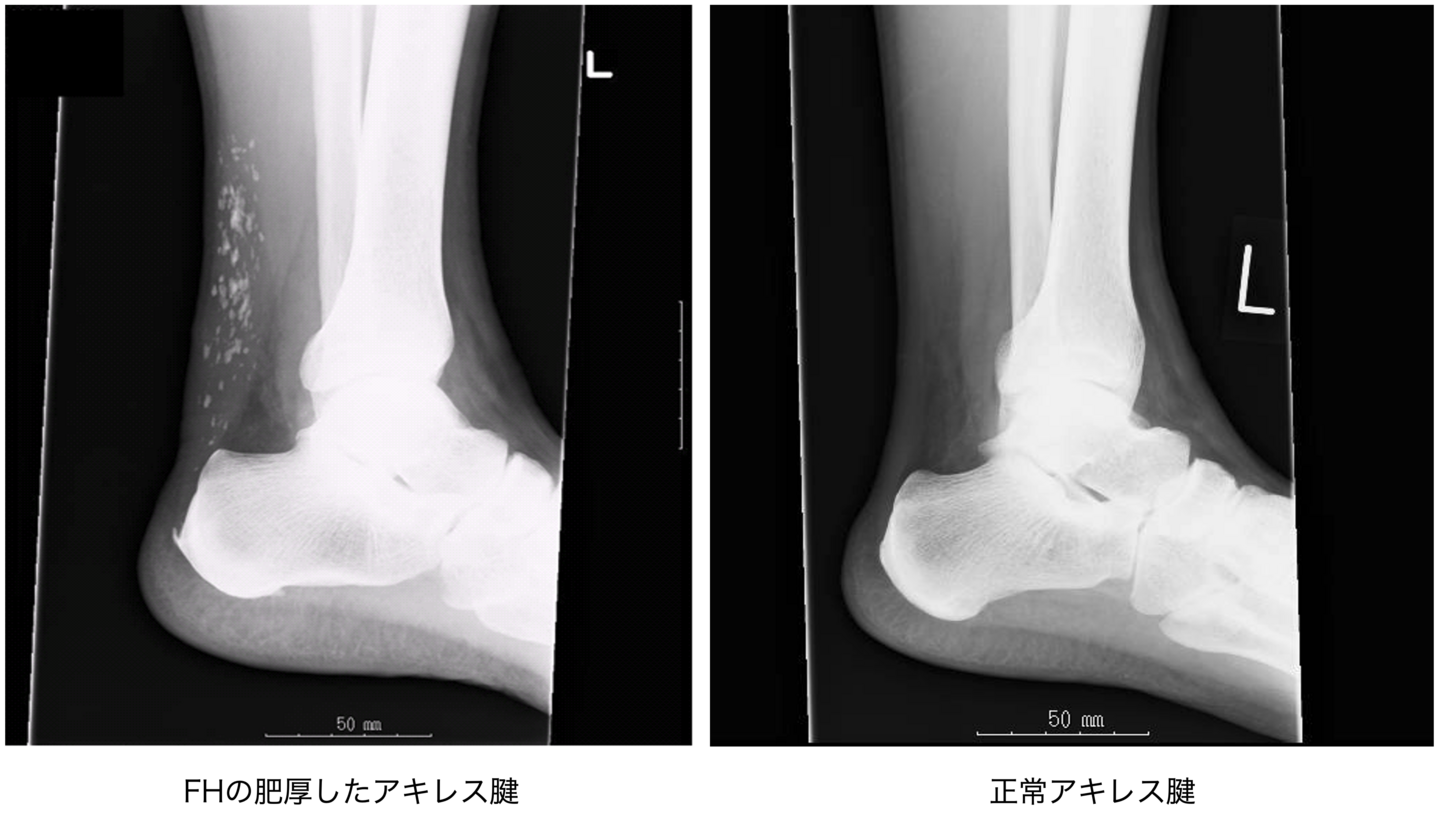

- アキレス腱肥厚はX線撮影により男性 8mm以上、女性7.5mm以上、あるいは、超音波により男性6mm以上、女性5.5mm以上にて診断する。

アキレス腱肥厚の診察

アキレス腱 X-P写真